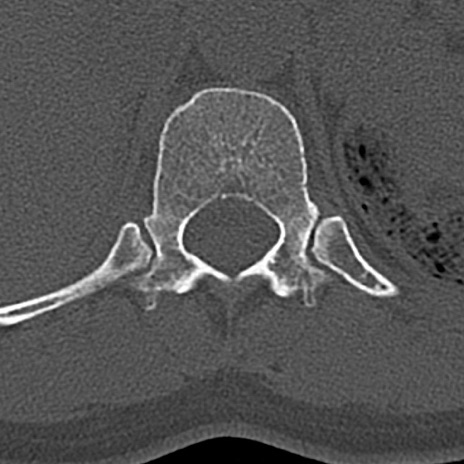

【整形】TIPS症例4 腰椎CT(横断像)

腰椎CT

横断像と矢状断像